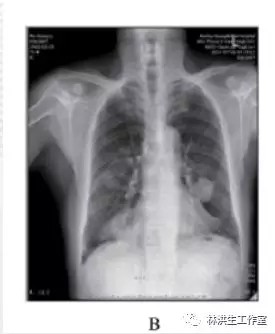

服药 1周后瘙痒减轻,皮疹减少,2个月后复查胸片提示肿瘤稍有缩小,之后继续按原方加减服用中药治疗,定期复查胸片提示肿瘤呈逐渐缩小趋势,同时瘙痒逐渐减轻明显,全身皮疹亦明显好转。2016年6月复查胸片,肿瘤明显缩小,仍有轻微瘙痒、已无皮疹。

B:2014 年 7 月 26 日复查,经治疗显示双肺肿物缩小;